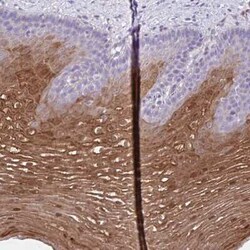

Cystatin B/Stefin B Antibody, Novus Biologicals™

Cystatin B/Stefin B Polyclonal antibody specifically detects Cystatin B/Stefin B in Human samples. It is validated for Immunohistochemistry, Immunohistochemistry (Paraffin)

| Immunohistochemistry 1:50 - 1:200, Immunohistochemistry-Paraffin 1:50 - 1:200 | |